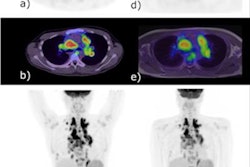

FIGO stage II pathologically confirmed moderately differentiated adenocarcinoma in a 57-year-old female patient. (A) Axial PET/MR images. (B) Axial MR T2-weighted images. (C) Axial PET/CT images. (D) Axial CT images. (E) Sagittal PET/MR images. (F) Sagittal PET/CT images. PET/MRI and MRI show the endometrial carcinoma invading the cervical stroma. PET/CT also shows the endometrial carcinoma invading the cervical stroma, yet the extension of the tumor is difficult to determine. The PET/MRI and PET/CT staging were consistent with the pathological stage, namely FIGO stage II. The white arrow indicates endometrial carcinoma. Image courtesy of BMC Cancer.

FIGO stage II pathologically confirmed moderately differentiated adenocarcinoma in a 57-year-old female patient. (A) Axial PET/MR images. (B) Axial MR T2-weighted images. (C) Axial PET/CT images. (D) Axial CT images. (E) Sagittal PET/MR images. (F) Sagittal PET/CT images. PET/MRI and MRI show the endometrial carcinoma invading the cervical stroma. PET/CT also shows the endometrial carcinoma invading the cervical stroma, yet the extension of the tumor is difficult to determine. The PET/MRI and PET/CT staging were consistent with the pathological stage, namely FIGO stage II. The white arrow indicates endometrial carcinoma. Image courtesy of BMC Cancer.In addition, an analysis of quantitative measures based on F-18 FDG PET/MRI radiotracer uptake by the tumors and nearby tissue were significantly different between stage I and stage III tumors, the authors wrote.